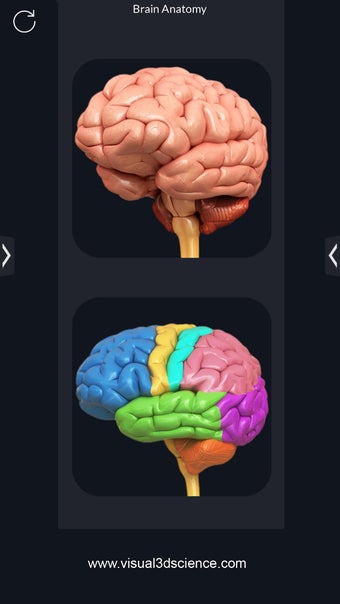

برنامج تشريح الدماغ Pro هو تطبيق تعليمي لدراسة تشريح الدماغ البشري. تم تصميم هذا التطبيق لكل من الطلاب الطبيين والجمهور العام. يتيح للمستخدمين استكشاف الدماغ من جميع الزوايا وعرض التشريح بطرق مختلفة. إنه أداة سهلة الاستخدام تتيح للمستخدمين تدوير 360 درجة والتكبير والتصغير وتحريك الكاميرا حول نموذج ثلاثي الأبعاد واقعي للغاية. يتيح للمستخدمين القدرة على تحديد الأجزاء وعرضها بالأشعة السينية وإخفائها وإظهارها وعرض الرسوم المتحركة في الوقت الحقيقي والرسم أو الكتابة على الشاشة ومشاركة لقطات الشاشة ونطق الصوت لجميع مصطلحات التشريح والمزيد. إنه تطبيق تعليمي مجاني.